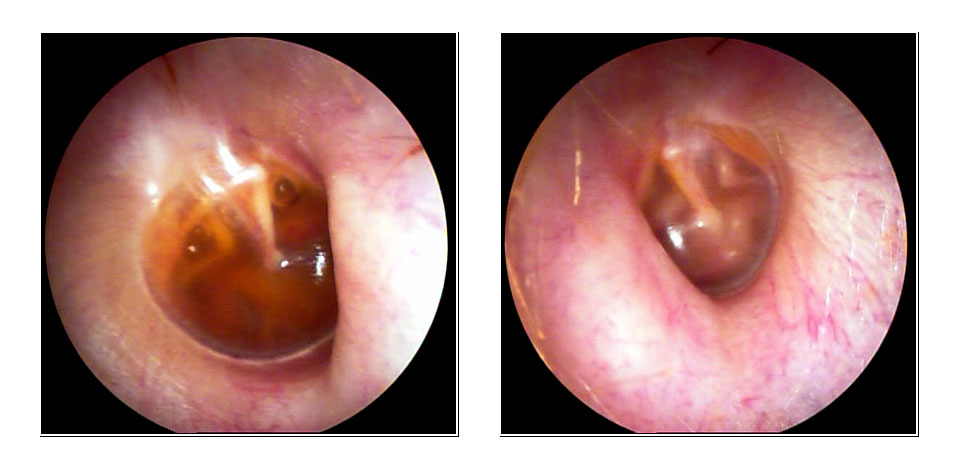

JFC Otitis media serosa de origen disbárico.

JFC Otitis media serosa izquierda.